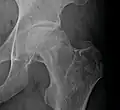

Radiography of avascular necrosis of left femoral head. Man of 45 years with AIDS. -

Nuclear magnetic resonance of avascular necrosis of left femoral head. Man of 45 years with AIDS. -